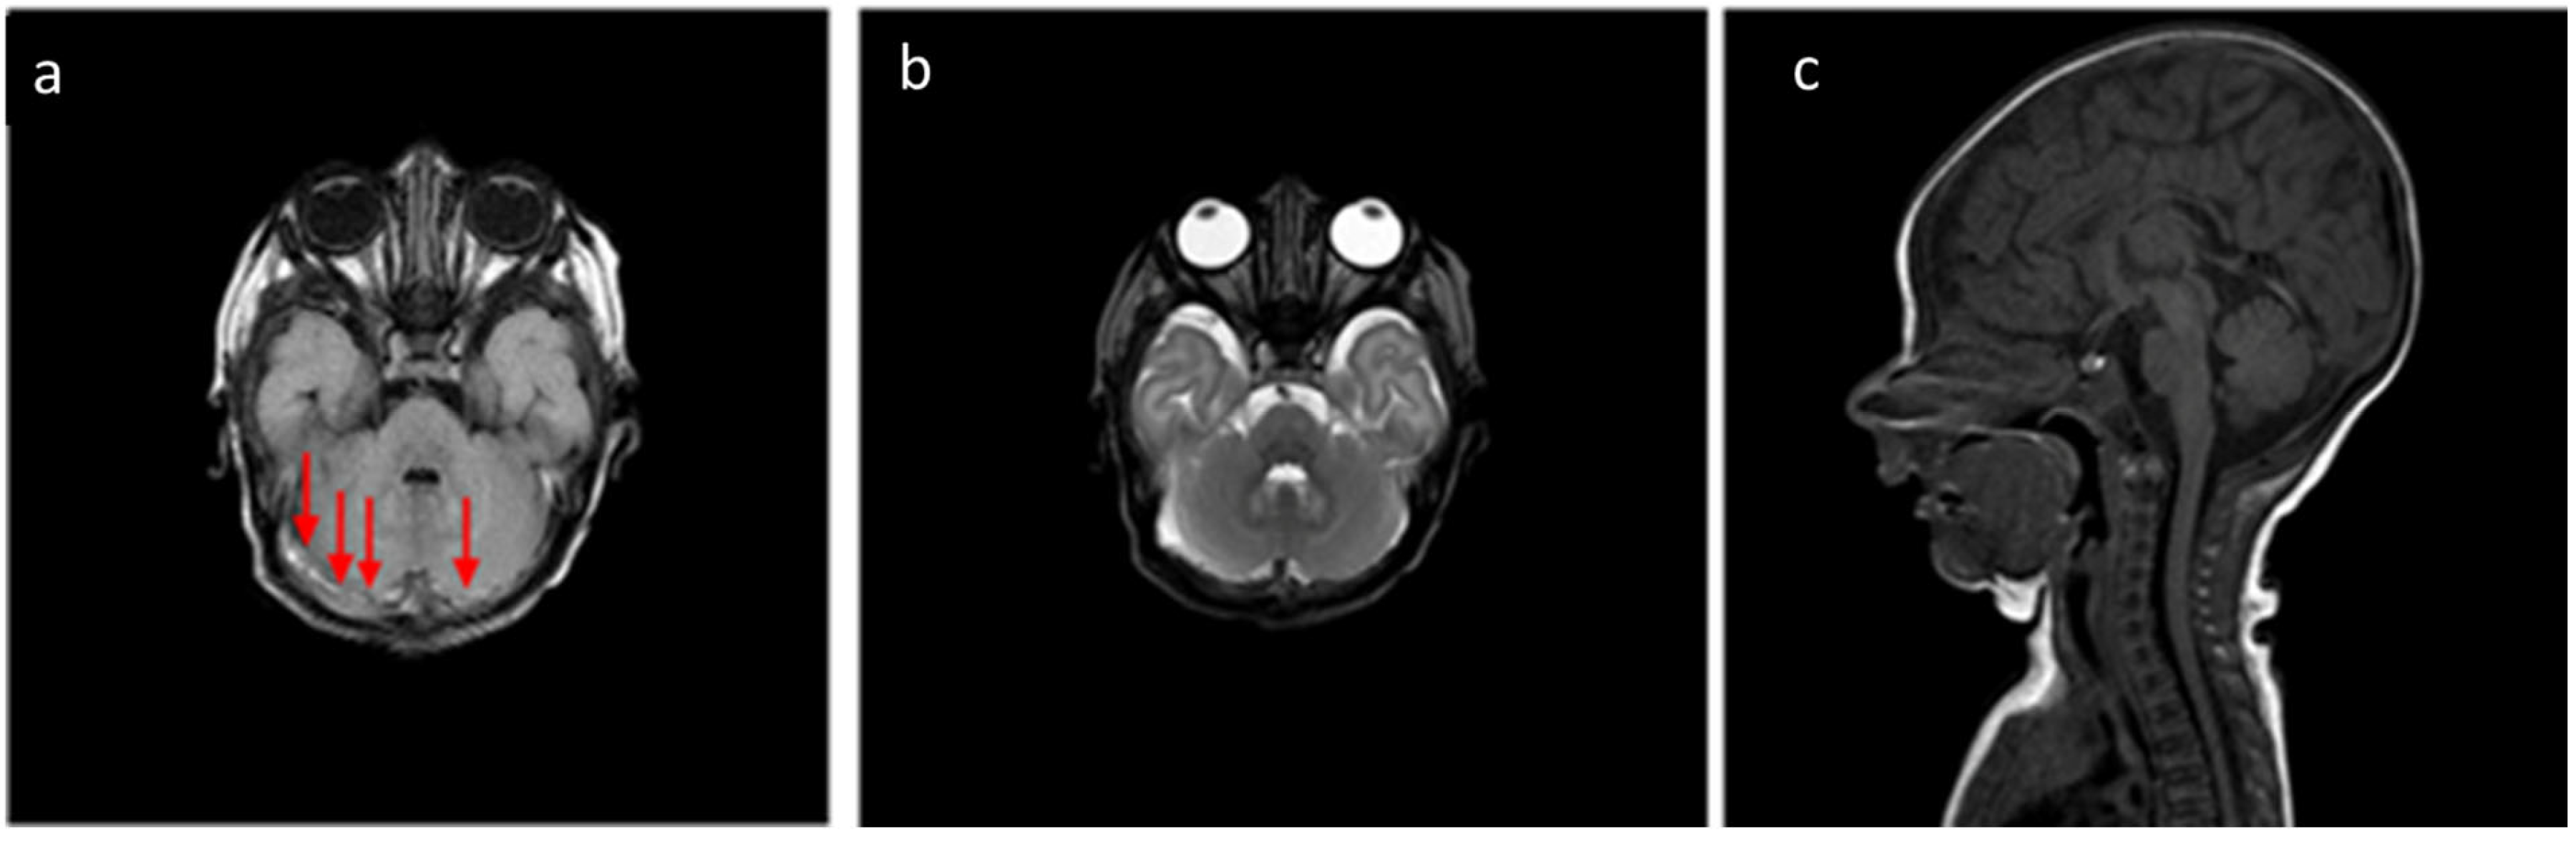

About the analysis of the SDH locations in the 32 patients which was the object of the study (Table 2, Table 3 and Table 4), the most common location was the cerebellum (31/32, 96.9%) followed by parietal and occipital lobes (19/32, 59.4%; 18/32, 56.2%, respectively), falx cerebri (11/32, 34.4%), tentorium cerebelli (10/32, 31.2%), temporal lobes (6/32, 18.7%), and finally, cervical and dorsal spine in the same patients (4/32, 12.5%, Figure 2, Figure 3, Figure 4 and Figure 5).

According to SDH locations, the patients were divided into supratentorial, infratentorial, both, and spinal canal (Table 5). Twenty-six patients (83%) showed simultaneous and/or bilateral co-involvement of multiple CNS areas. Cerebellum involvement occurred in almost all patients (31/32, 96.9%) except in one 3-day-old infant. In the cerebellum, bilateral involvement was observed in 78% (18/23) of males and 44.5% (4/9) of females. Parietal and occipital SDH were predominantly bilateral in both genders (68.7% and 100%, males and females, respectively), whereas tentorial hemorrhages were more frequently unilateral. The SDH of the falx cerebri and temporal area were more often bilateral in females, while males exhibited a higher prevalence of unilateral involvement in these areas.

The most frequent localization was the cerebellum (31/32, 96.9%), with a single unaffected case, while no cases with only supratentorial localization were detected. The spinal canal represented the least involved site (4/32, 12.5%), with both cervical and dorsal involvement in the same patients. In particular, we observed very thin hematomas with anterior and/or posterior distribution. These cases were associated with a simultaneous involvement of both supratentorial and infratentorial CNS structures. After a month, these four spinal SDH patients were re-evaluated, and a complete resolution with restitutio ad integrum was reached.